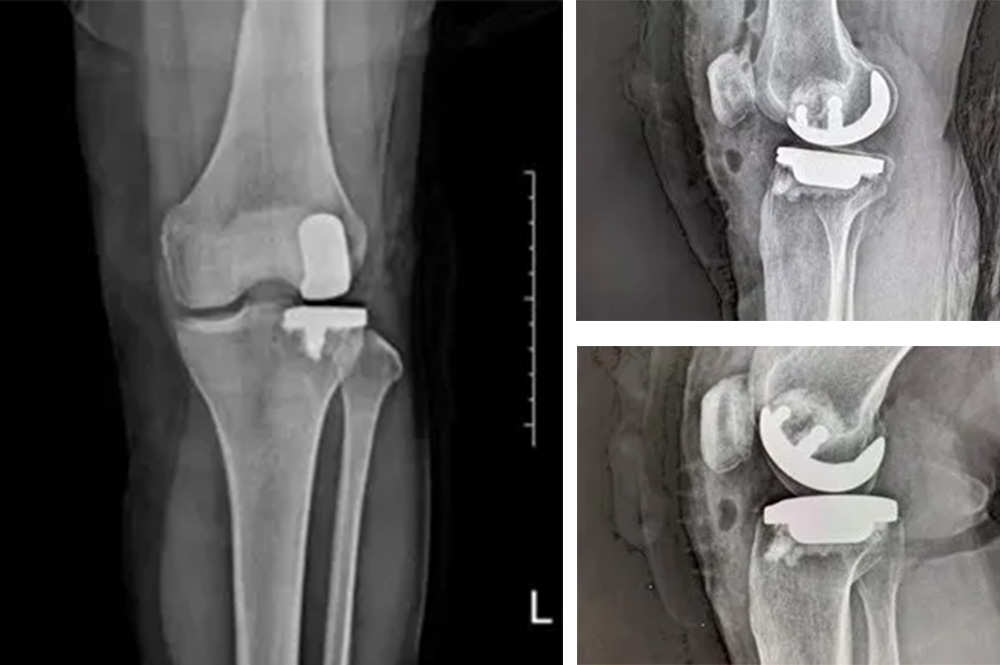

我院骨科主任羅醫(yī)生介紹,膝關(guān)節(jié)分為內(nèi)側(cè)、外側(cè)和髕股三個(gè)間室。鮑奶奶的問題主要集中在膝關(guān)節(jié)外側(cè)間室,而內(nèi)側(cè)和髕股關(guān)節(jié)相對(duì)完好。

“傳統(tǒng)全膝關(guān)節(jié)置換會(huì)切除所有關(guān)節(jié)面,而單髁置換只替換病變的部分,保留了健康的韌帶和軟骨,更符合‘精準(zhǔn)醫(yī)療’理念。”羅醫(yī)生說。

經(jīng)過詳細(xì)的體格檢查、影像學(xué)評(píng)估和三維重建,醫(yī)療團(tuán)隊(duì)確認(rèn)鮑奶奶的情況非常適合進(jìn)行膝外側(cè)單髁置換術(shù)。這種微創(chuàng)手術(shù)創(chuàng)傷小、恢復(fù)快,能夠最大程度保留膝關(guān)節(jié)的自然結(jié)構(gòu)和功能。

手術(shù)當(dāng)天,骨科團(tuán)隊(duì)采用微創(chuàng)切口,僅約8厘米,遠(yuǎn)小于傳統(tǒng)全膝關(guān)節(jié)置換手術(shù)切口。術(shù)中精準(zhǔn)定位,僅置換病變的膝關(guān)節(jié)外側(cè)間室。

手術(shù)使用了最新的單髁假體系統(tǒng),這種假體設(shè)計(jì)更符合人體工程學(xué),能夠更好地恢復(fù)膝關(guān)節(jié)的自然運(yùn)動(dòng)軌跡。

膝外側(cè)單髁置換術(shù)是膝關(guān)節(jié)置換領(lǐng)域的重要進(jìn)展。與全膝關(guān)節(jié)置換相比,它具有明顯優(yōu)勢:手術(shù)創(chuàng)傷小,僅置換病變部分;保留更多自然結(jié)構(gòu)和韌帶;術(shù)后恢復(fù)快,住院時(shí)間短;術(shù)后膝關(guān)節(jié)感覺更自然,活動(dòng)度更好。